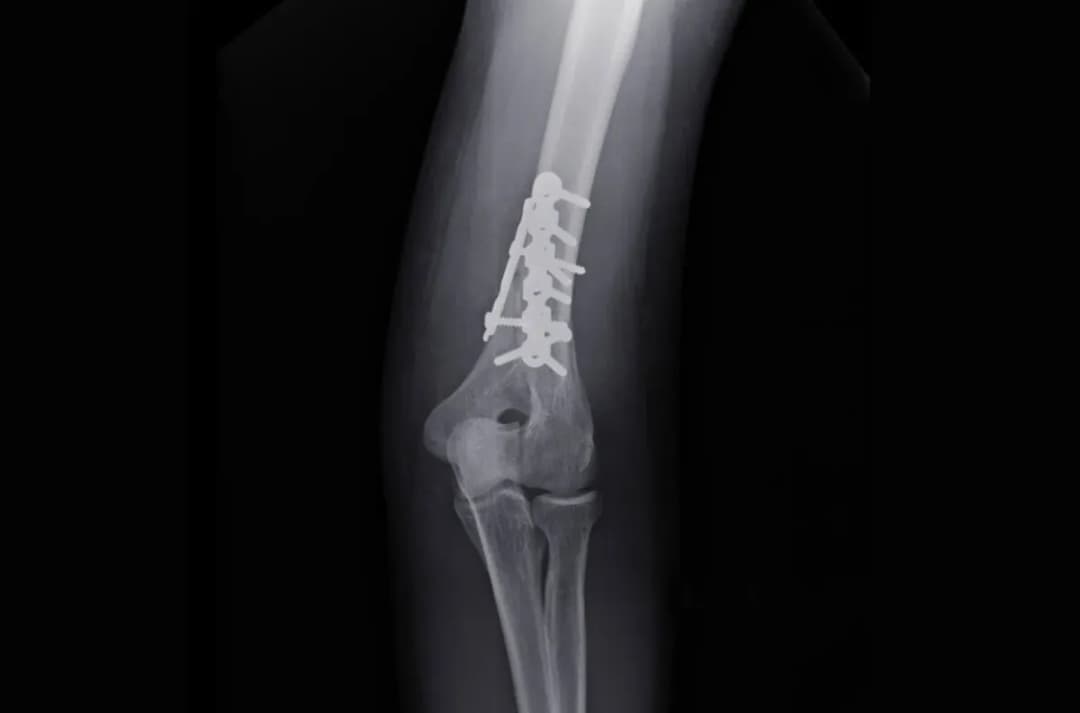

Różnice w rehabilitacji po leczeniu zachowawczym i operacyjnym

Rehabilitacja różni się w zależności od metody leczenia. W przypadku leczenia zachowawczego, rehabilitacja może rozpocząć się po 3-4 tygodniach, wprowadzając na przykład ćwiczenia izometryczne. Z kolei po leczeniu operacyjnym, rehabilitację można rozpocząć już po 3 tygodniach, co pozwala na szybsze wzmocnienie mięśni i stawów. Takie różnice w podejściu do rehabilitacji są istotne dla skuteczności całego procesu zdrowienia.